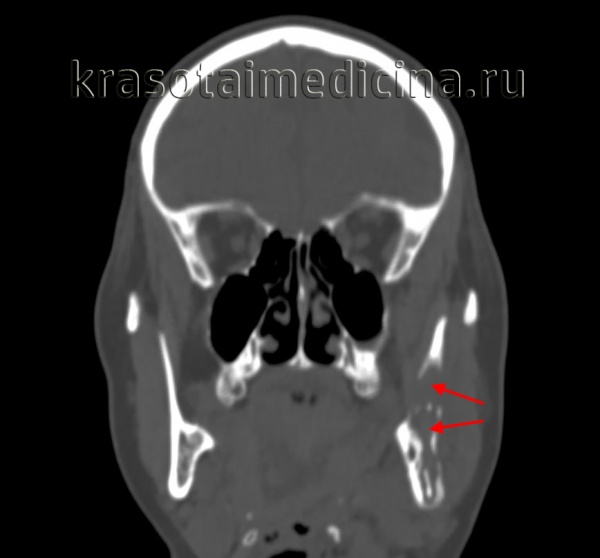

(Слева) КТ в костном окне, аксиальная проекция. По сравнению с нормальным левым овальным отверстием правое овальное отверстие увеличено в размерах. Расширение отверстия обусловлено распространением злокачественной опухоли по нижнечелюстному нерву.

(Справа) КТ с КУ, аксиальная проекция. По волокнам нижнечелюаного нерва опухоль распространилась в тройничную полость и среднюю черепную ямку. Обратите внимание, что с левой стороны тройничная полость имеет нормальную плотность, соответствующую плотности спинномозговой жидкости.